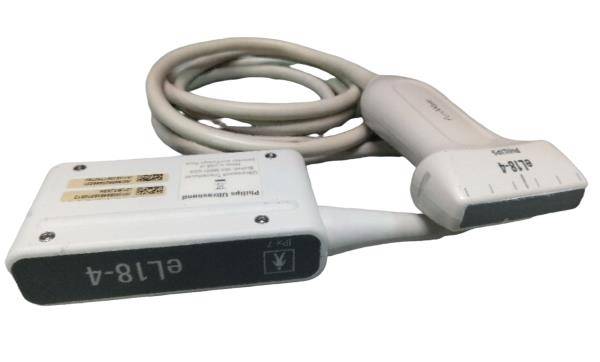

Seller Notes:âFully functional. Tested using a GE Logiq 9 with a breast phantom. Shows signs of use. Includes everything shown.â

Model: GE 4D8C 3D/4D Curved Array 3.5-9MHz Ultrasound Tra

The GE 4D8C ultrasound transducer probe operates within a frequency range of 3.5-9MHz, making it ideal for high-resolution imaging. This device harnesses advanced 4D capabilities, allowing healthcare professionals to visualize complex anatomical structures in real-time. Consequently, it enhances diagnostic accuracy and aids in better patient care. Users can expect clear and detailed images, which significantly improve evaluation and treatment processes.

This ultrasound transducer is versatile and adapts to various clinical applications, including obstetrics, cardiology, and vascular imaging. Medical practitioners can utilize the instrument for routine examinations and specialized diagnostics. Another advantage is its curved array design, which provides an extended field of view, allowing for easier and quicker assessment of the patient's condition. Hence, it streamlines workflows in busy clinical environments.

The GE 4D8C ultrasound probe integrates user-friendly features that make it easy to operate, even for novice users. The ergonomic design ensures comfort during long procedures, while the intuitive controls provide a seamless experience for the operator. Additionally, the device is lightweight, promoting ease of handling. Therefore, healthcare providers can maintain focus on patient outcomes, knowing that they have reliable equipment at their disposal.